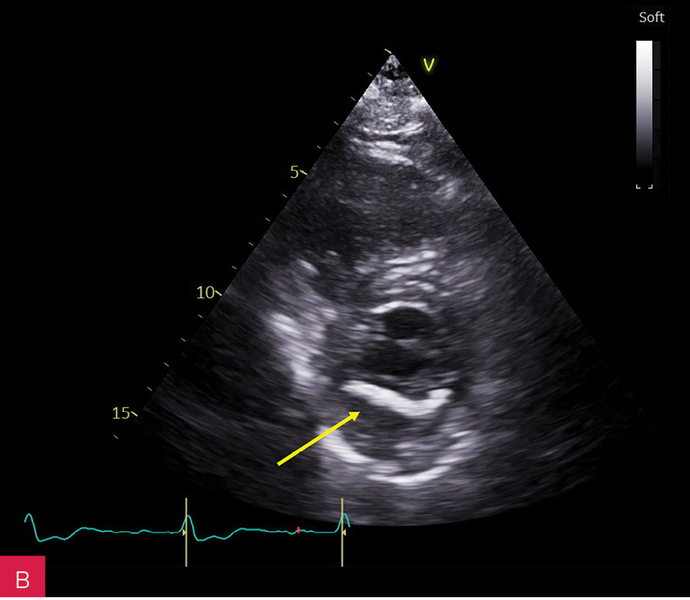

Rycina 1A, B. Zwapnienie w pierścieniu mitralnym (MAC) u podstawy tylnego płatka mitralnego w projekcji przymostkowej w osi długiej LAX (A) i w osi krótkiej SAX (B)